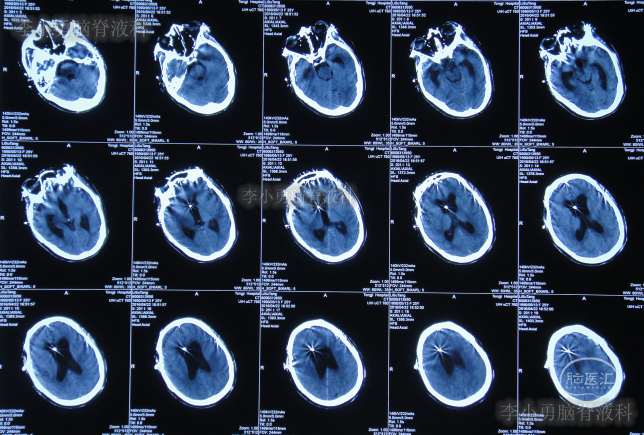

家属为进一步明确病因即2016年4月4日,第2次就诊并住入第二家的上海市静安区的某三甲医院,复查头颅影像后(图-3、图-4),给予按癫痫进行治疗。

图-4:2016年4月4日头颅影像